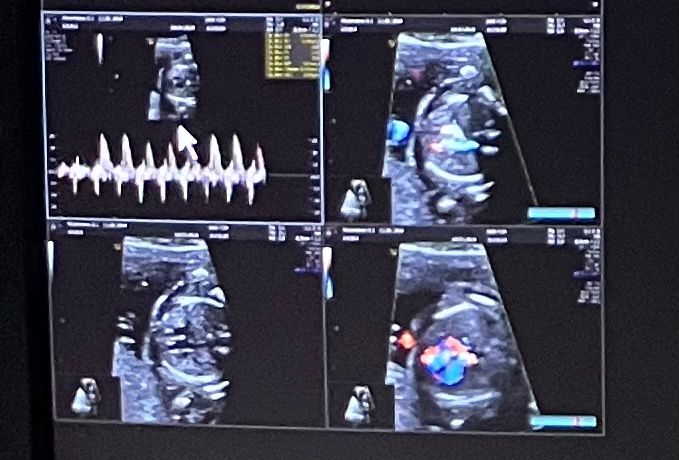

Не знаю, уж если вы в узистке усомнились, в человеке с образованием, что тут с обывателей возьмешь...ничего не ясно, но я бы предположила, что это писечка девочки 😁

Тут не видно пол

Это грудная клетка помоему на снимках

Мне кажется это головной мозг

Olga dey, кстати да, только не мозг, а череп скорее с темечком

Мне кажется вообще что это голова и вид сверху))